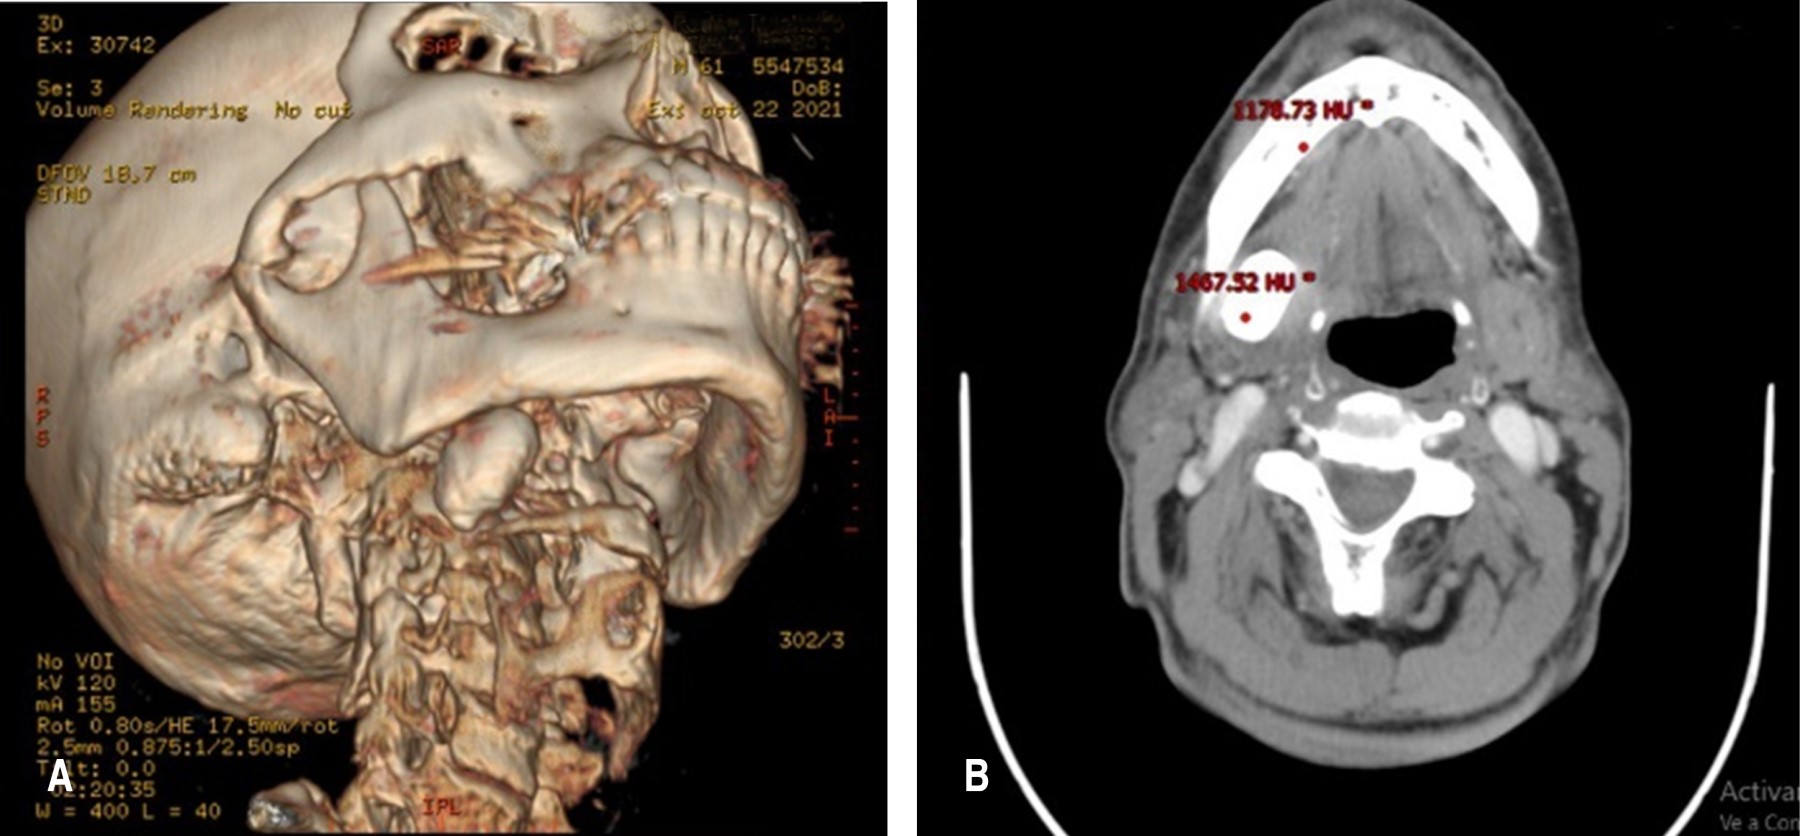

En el examen clínico se observó asimetría facial asociada al tercio inferior en la región submandibular derecha debido a una lesión nodular de aproximadamente 10 cm de diámetro, de bordes definidos, normocrómico, normotérmico, indurado, no doloroso a la palpación y móvil (Figura 1); al estudiar la tomografía computarizada de cortes axiales, sagitales y coronales se advirtió una imagen hiperdensa circunscrita de aproximadamente 6 cm en la cara medial del cuerpo mandibular derecho, que arrojó 1,500 unidades Hounsfield, lo cual se vincula con una lesión de contenido calcificado, además, según su ubicación, se puede saber de qué tipo de lesión se trata (Figura 2).

Las radiografías simples representan un método de estudio complementario con una alta sensibilidad para la localización de lesiones mineralizadas en el tercio medio e inferior facial por imágenes radiopacas,6 incluso se pueden utilizar ultrasonidos de glándulas salivales para no sólo ubicar el sialolito, sino también para determinar el estado general del parénquima que lo acoge;7 sin embargo, la tomografía computarizada simple permite al clínico identificar la topografía anatómica del lecho quirúrgico, lo que representa una ventaja en la decisión del abordaje planteado para la sialoadenectomía, en nuestro caso utilizamos una tomografía con contraste que nos permitió, además de lo ya antes mencionado, corroborar que la lesión no estaba perfundida.4